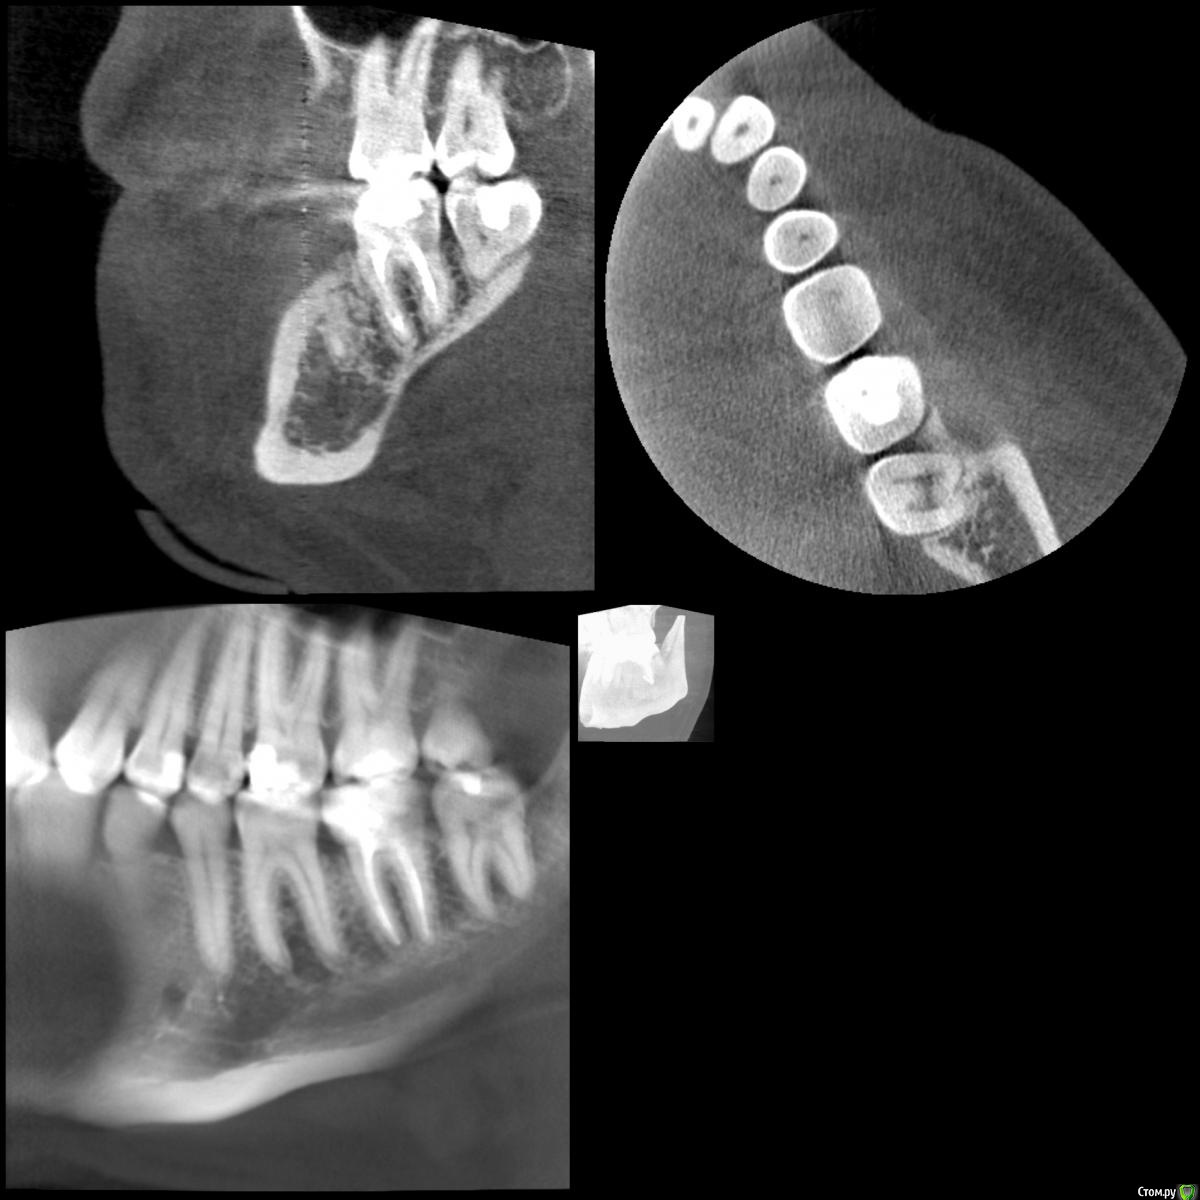

В августе прошлого года у меня начал сильно болеть десны и зуб на фоне обострения поллиноза. Врач обнаружил пульпит в болевшем зубе и еще несколько очагов кариеса по КТ. Очаги кариеса были запломбированы, в пульпитом 37 зубе было проведено депульпирование и пломбировка каналов. При пломбировке каналов врач что-то прижигал нагретой палочкой, раньше я думал, что при пломбировке использовалась гуттаперча. После лечения ощущались боли при надкусывании в 36 зубе несколько недель, на которые я не обращал внимания.

Прикладываю срезы с КТ от начала января 2017, скан распечатки прицельного снимка 36 37 зуба от ноября 2016.